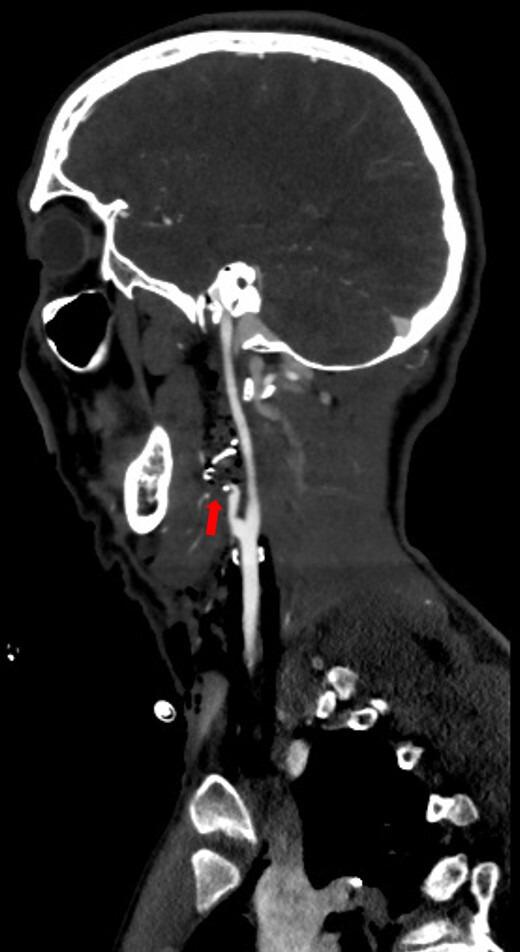

Management of penetrating neck injury to zone III in an initially unstable patient.

Trauma Surg Acute Care Open. 2025 May 16;10(2):e001724. doi: 10.1136/tsaco-2024-001724. eCollection 2025.